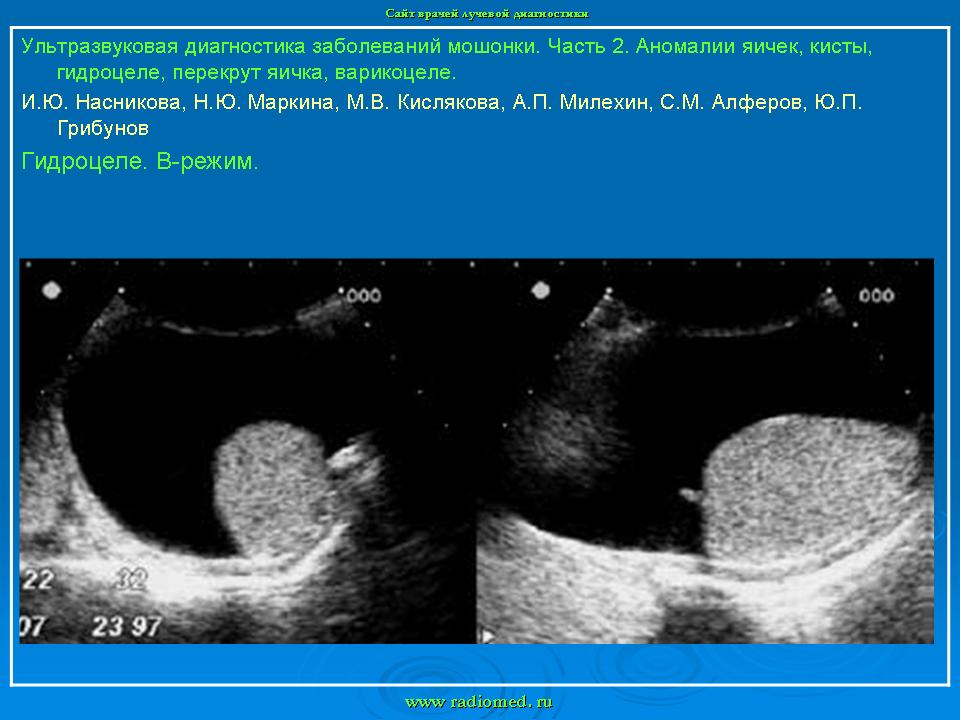

УЗИ. УЗ - диагностика заболеваний мошонки. +

УЗ - диагностика заболеваний мошонки.